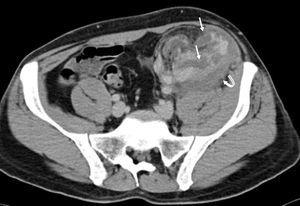

An emergency Doppler echocardiogram was performed showing the graft of 121 mm in the left iliac fossa (LIF) with increased cortical echogenicity, good perfusion, RF: 1. An organized perirenal haematoma of 93 x 37 x 60 mm was identified. To complete the study, a CT scan with contrast was performed showing enhancement of all the kidney with 2 hypoechoic linear lesions. These were interpreted as a fracture of the anterior pole of the graft (Figures 1 and 2). No aneurysm or kidney tumours were observed. In view of the patient being haemodynamically stable and the diagnosis of advanced kidney rupture, emergency surgery was ruled out. An initial session of haemodialysis was performed; diuresis began again after 48 h with progressive improvements in the analytical parameters. The diagnosis of AR was ruled out given the patient’s good progress without having taken other therapeutic measures and the fact that his immunosuppressor levels were within the normal range.

Figure 2. CT scan of the graft showing hypoechoic linear lesions compatible with fracture of the anterior pole (thin arrows)